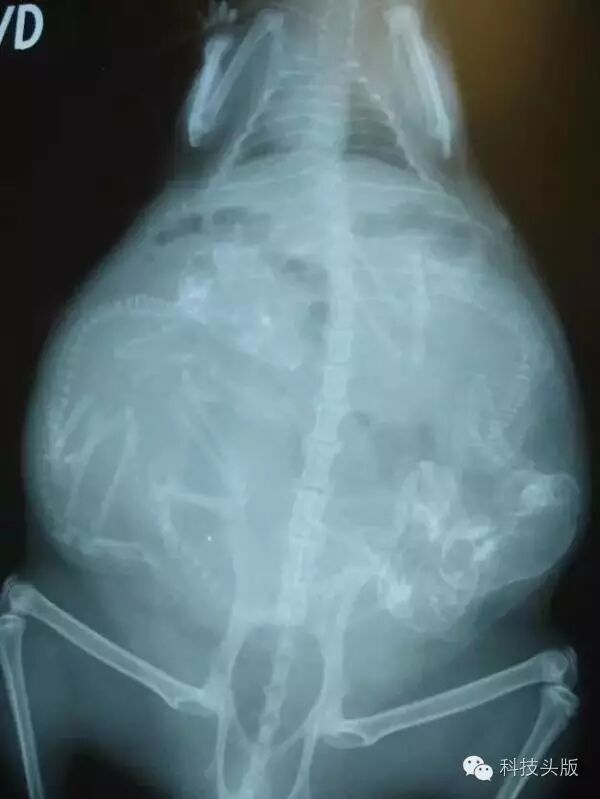

这是喵大王。看猫宝宝……好挤啊……